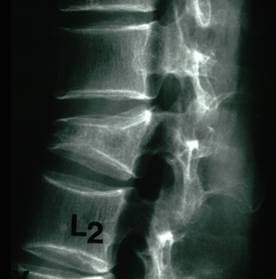

На представленных рисунках приводится пример выполения вертебропластики у больного с патологическим переломом поясничного позвонка вследствие остеопороза. На исходной рентгенограмме виден компрессионный перелом позвонка, а на правом нижнем снимке в разрушенный позвонок введен цемент (белое пятно), который частично восстановил высоту позвонка.

До вертебропластики

Компрессионный перелом поясничного позвонка вследствие остеопороза